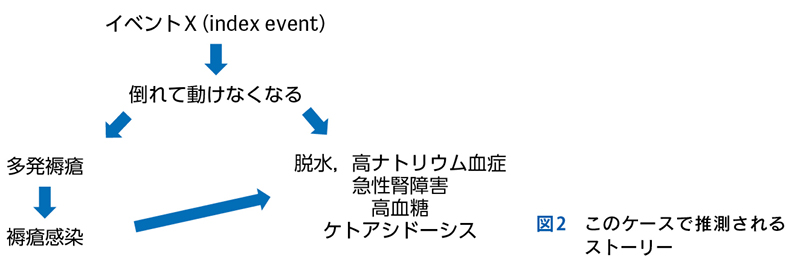

Case 1

独居の高齢者が自宅内で倒れている状態で発見され搬送された。最終健常は5日前。頻脈,SpO2低下,意識障害,感染徴候を伴う褥瘡,急性腎障害,高ナトリウム血症,クレアチンキナーゼ高値,炎症反応亢進,膿尿がみられている。

▶ この患者は何らかのイベントを契機に動けなくなり,長時間倒れていたものと推測される。多数ある「プロブレム」の中には,最初のイベントに直接起因するものもあるかもしれないが,大部分は倒れていた結果として生じてきたもの(最初のイベントの診断という観点では「ノイズ」)だろう。こういった患者が「脱水症」とか「横紋筋融解症」としてのみ治療されているケースをよく見かけるが,これは表層に現れた二次的,三次的な現象を取り上げているだけであり,最初のイベントの鑑別と治療が本来必要である。